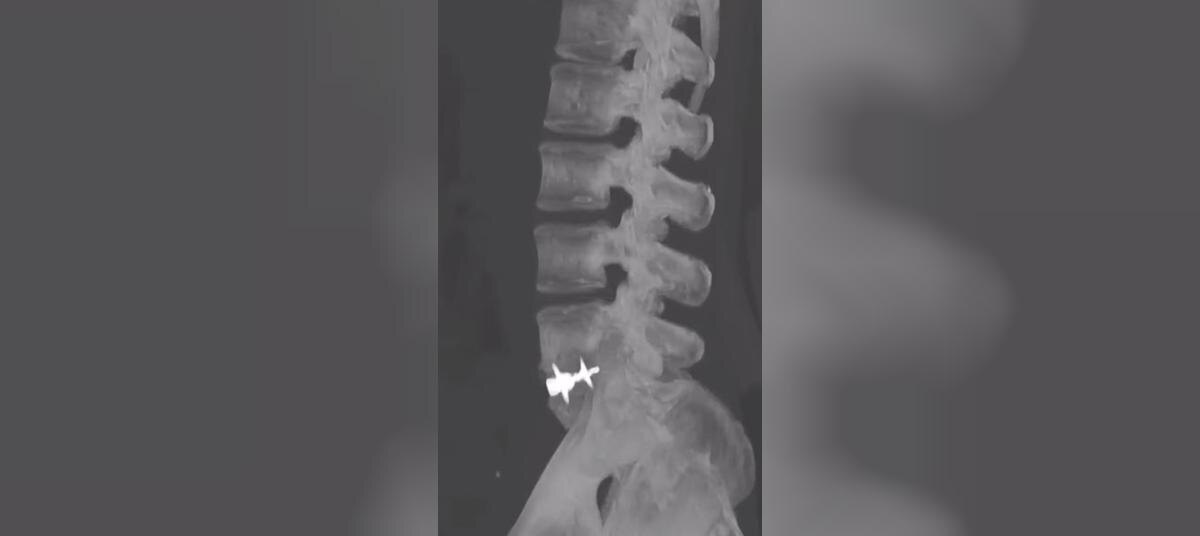

Фото: Минздрав Воронежской области

МРТ показала грыжу межпозвонкового диска. КТ поясницы выявила нестабильный спондилолистез. Это смещение позвонка назад более чем на 5 мм. Также выяснилось, что из-за проблем с поясницей у пациентки немела нога.

Врачи провели нейрохирургическую операцию — передний межтеловой спондилодез поясничного отдела позвоночника. Суть вмешательства с том, что позвонки как будто «спаивают» между собой. В ходе заживления болезненные позвонки становятся неподвижными.

Также женщине удалили грыжу и установили протез через переднюю брюшную стенку. Благодаря операции удалось купировать боль и достичь стабилизации позвоночника.